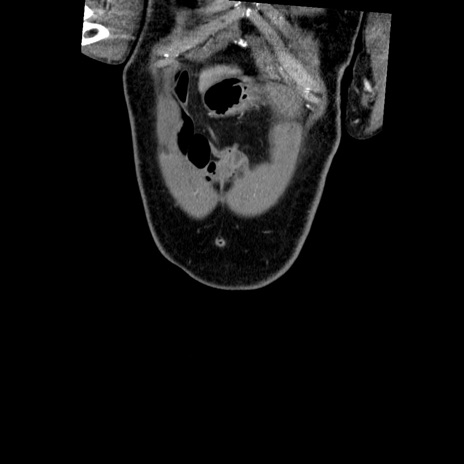

横断像

【症例】50歳代男性

【主訴】腹痛

【現病歴】AVMからの被殻出血のため回復期リハ病棟入院中。 本日午後3時頃急に下腹部痛が出現した。

【既往歴】AVM、被殻出血、虫垂炎、高血圧

【身体所見】意識晴明、左半身不全麻痺、会話の理解は良好、36.5°C、腹部:膨隆、全体に板状硬、下腹部正中に圧痛点あり、反跳痛-、筋性防御不明、右下腹部にope scar

【データ】WBC 9400、CRP 0.06